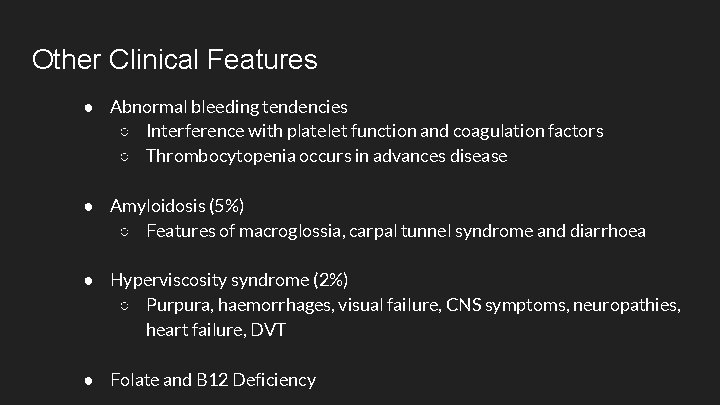

Other Clinical Features ● Abnormal bleeding tendencies ○ Interference with platelet function and coagulation factors ○ Thrombocytopenia occurs in advances disease ● Amyloidosis (5%) ○ Features of macroglossia, carpal tunnel syndrome and diarrhoea ● Hyperviscosity syndrome (2%) ○ Purpura, haemorrhages, visual failure, CNS symptoms, neuropathies, heart failure, DVT ● Folate and B 12 Deficiency